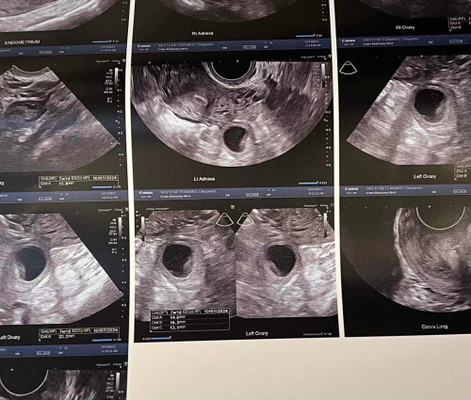

6 สัปดาห์หมอซาวไม่เจอน้อง นัดใหม่อีก 2 สัปดาห์ แบบนี้จะมีโอกาสเห็นน้องมั้ยค่ะ